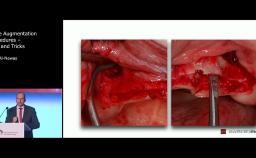

In this lecture Dr. Buser describes the most common causes of esthetic implant failures, in particular how malpositioning of the implant affects esthetic outcomes and which kind of mistakes are commonly made. Most such cases require implant removal, which results in creation of a bone defect and, very often, a soft tissue defect, i.e., lack of keratinized mucosa. He describes techniques of implant removal, methods to reestablish keratinized tissue, and factors which determine sequence of procedures needed to improve the outcome.

define treatment options for correction of esthetic failures

discuss factors which determine selection of most appropriate treatment option